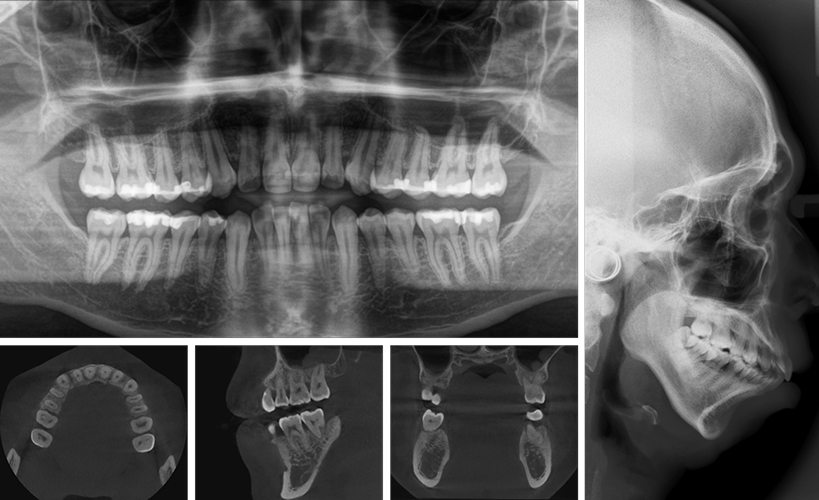

Supports panoramic, cephalometric, periapical, bitewing, CBCT, and intraoral camera images.

View panoramic, periapical, cephalometric, and CBCT in one interface.

Compare multiple images side-by-side for accurate diagnosis.

Sugar Dental PACS offers purpose-built tools for dental diagnostics—zoom, pan, contrast control, sharpening, endodontic length measurement, implant planning aids, and cephalometric angle analysis. Easily annotate abnormalities, mark treatment areas, and manage CBCT slices with fast, smooth interaction.

CBCT slice viewer, cine mode for sequential frames.